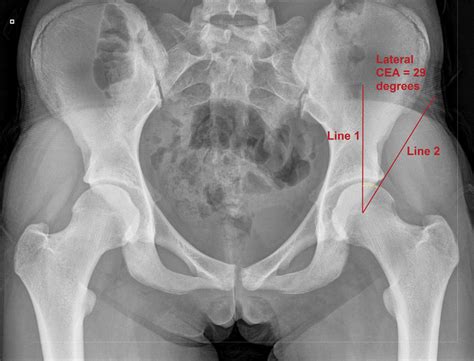

The Best Center Edge Angle Ideas

The Best Center Edge Angle Ideas. Wiberg’s or center edge (ce) angle is formed at the juncture of the perkin line with line drawn from the center of the femoral head to the outer edge of the acetabular roof. Less than 20 deg indicates severe dysplasia; Angle formed by perkin's line and a line from the center of the femoral head to the lateral edge of the acetabulum. Edge early learning angle vale, previously known as where we grow, provides quality childcare and kindergarten programs tailored to children 6 weeks and up. Compare normal (figure 1) with abnormal over coverage.